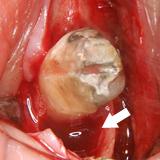

歯槽膿漏 | ||

| 歯槽膿漏によって失われた骨が再生しています。 | ![]() |

![]() |

【術前】 |

【術後】 |